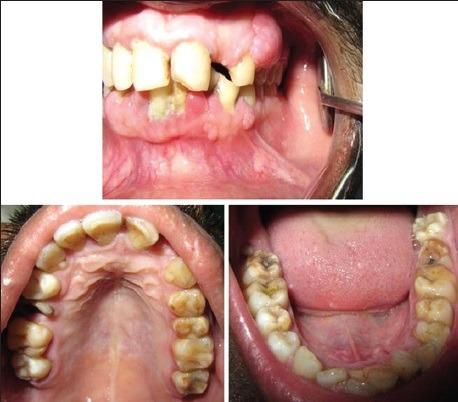

Tuberous sclerosis complex is an unusual autosomal dominant neurocutaneous syndrome characterized by the development of benign tumors affecting different body systems affecting the brain, skin, retina, and viscera. It is characterized by cutaneous changes, neurologic conditions, and the formation of hamartomas in multiple organs leading to morbidity and mortality. The most common oral manifestations are fibromas, gingival hyperplasia, and enamel hypoplasia. The management of these patients is often multidisciplinary involving specialists from various fields. Here, we present a case report of a 26-old-year male patient with characteristic clinical, radiological, and histological features of tuberous sclerosis complex.

结节性硬化症是一种罕见的常染色体显性神经皮肤综合征,其特征是在影响大脑、皮肤、视网膜和内脏的不同身体系统中出现良性肿瘤。它的特点是皮肤改变、神经系统疾病以及多个器官中错构瘤的形成,从而导致发病和死亡。最常见的口腔表现是纤维瘤、牙龈增生和釉质发育不全。这些患者的治疗通常需要多学科参与,涉及各个领域的专家。在此,我们报告一例26岁男性患者,具有结节性硬化症的典型临床、放射学和组织学特征。